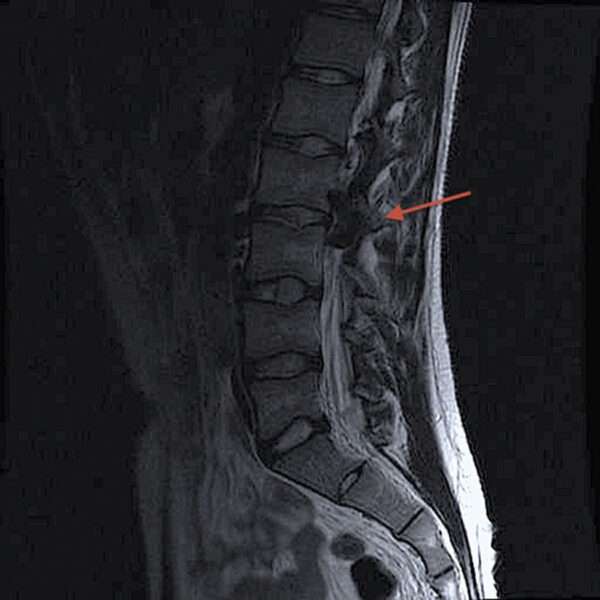

La resonancia magnética de columna puede no detectar la fístula arteriovenosa dural espinal en todos los casos; sin embargo, muchas veces se observan hiperintensidades en T2 en la médula espinal o vacíos de flujo perimedular, lo que sugiere la presencia de una alteración vascular. La mielografía, que se realiza con el paciente en posición prono y supino, puede revelar defectos de llenado serpiginosos debido a la presencia de vasos sanguíneos dilatados, lo que es indicativo de la fístula.

Para confirmar el diagnóstico y planificar el tratamiento adecuado, se requiere arteriografía selectiva espinal. La mayoría de estas lesiones son extramedulares y se localizan por detrás de la médula espinal, ya sea intradural o extradurales. El tratamiento de estas fístulas es relativamente sencillo y puede incluir la ligadura de los vasos de alimentación y la excisión de la anomalía fistulosa, o bien, la realización de procedimientos de embolización.